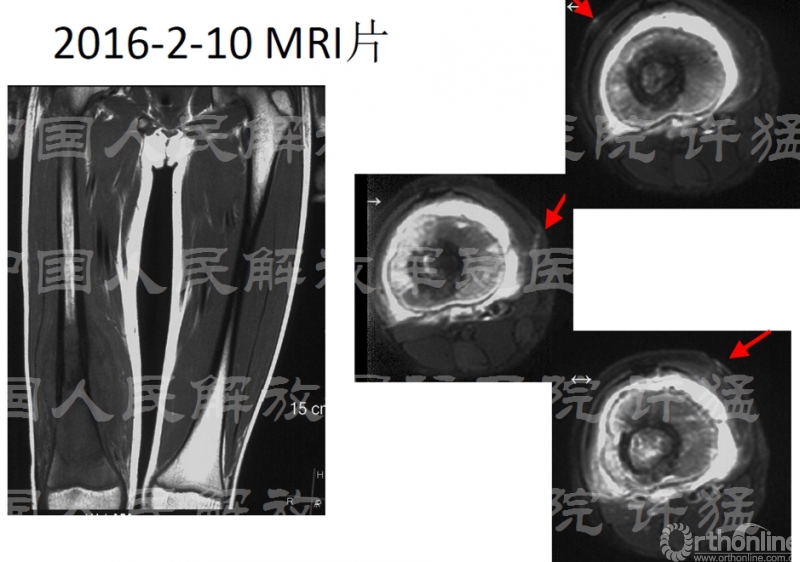

入院前检查:

核磁显示股四头肌伸膝装置受到肿瘤累及